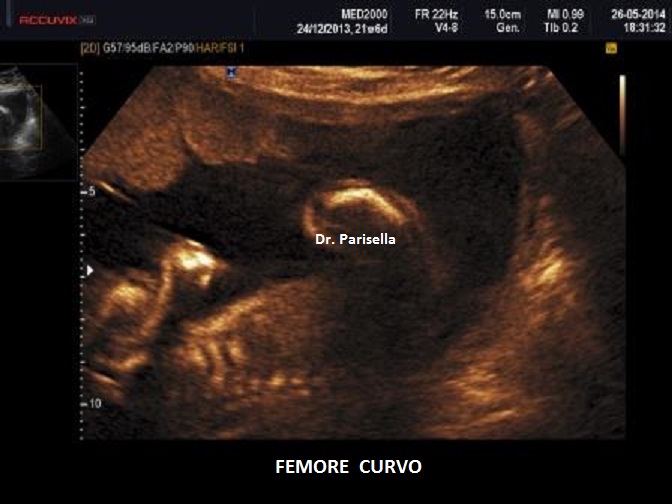

Quella che interessa dal punto di vista della diagnosi ecografica prenatale è l'Osteogenesi Imperfetta tipo II (OMIM 166210) caratterizzata da fragilità ossea con fratture multiple, micromelia severa dovuta alle fratture delle ossa lunghe, ipoplasia toracica severa a volte con fratture costali, ipomineralizzazione diffusa del cranio.  Ecograficamente si manifesta con ossa corte, ricurve e fratturate (le ossa fratturate si presentano angolate); ossa craniche scarsamente ossificate (tanto che la volta cranica può avere una ecogenicità simile a quella della linea mediana) con conseguente migliore evidenza e definizione delle strutture cerebrali e segno caratteristico la deformabilità della teca cranica.;  ipoplasia toracica con fratture costali; IUGR; movimenti fetali scarsi.